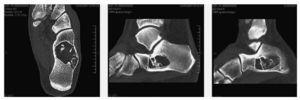

Se realiza estudio radiográfico simple en la misma revisión y se observa imagen radiolucente en cuello de calcáneo con trabéculas óseas en su interior (fig. 1).

Figura 1 Lesión radiolúcida de bordes bien definidos con trabéculas gruesas en su interior localizada en el cuerpo-cuello de calcáneo.